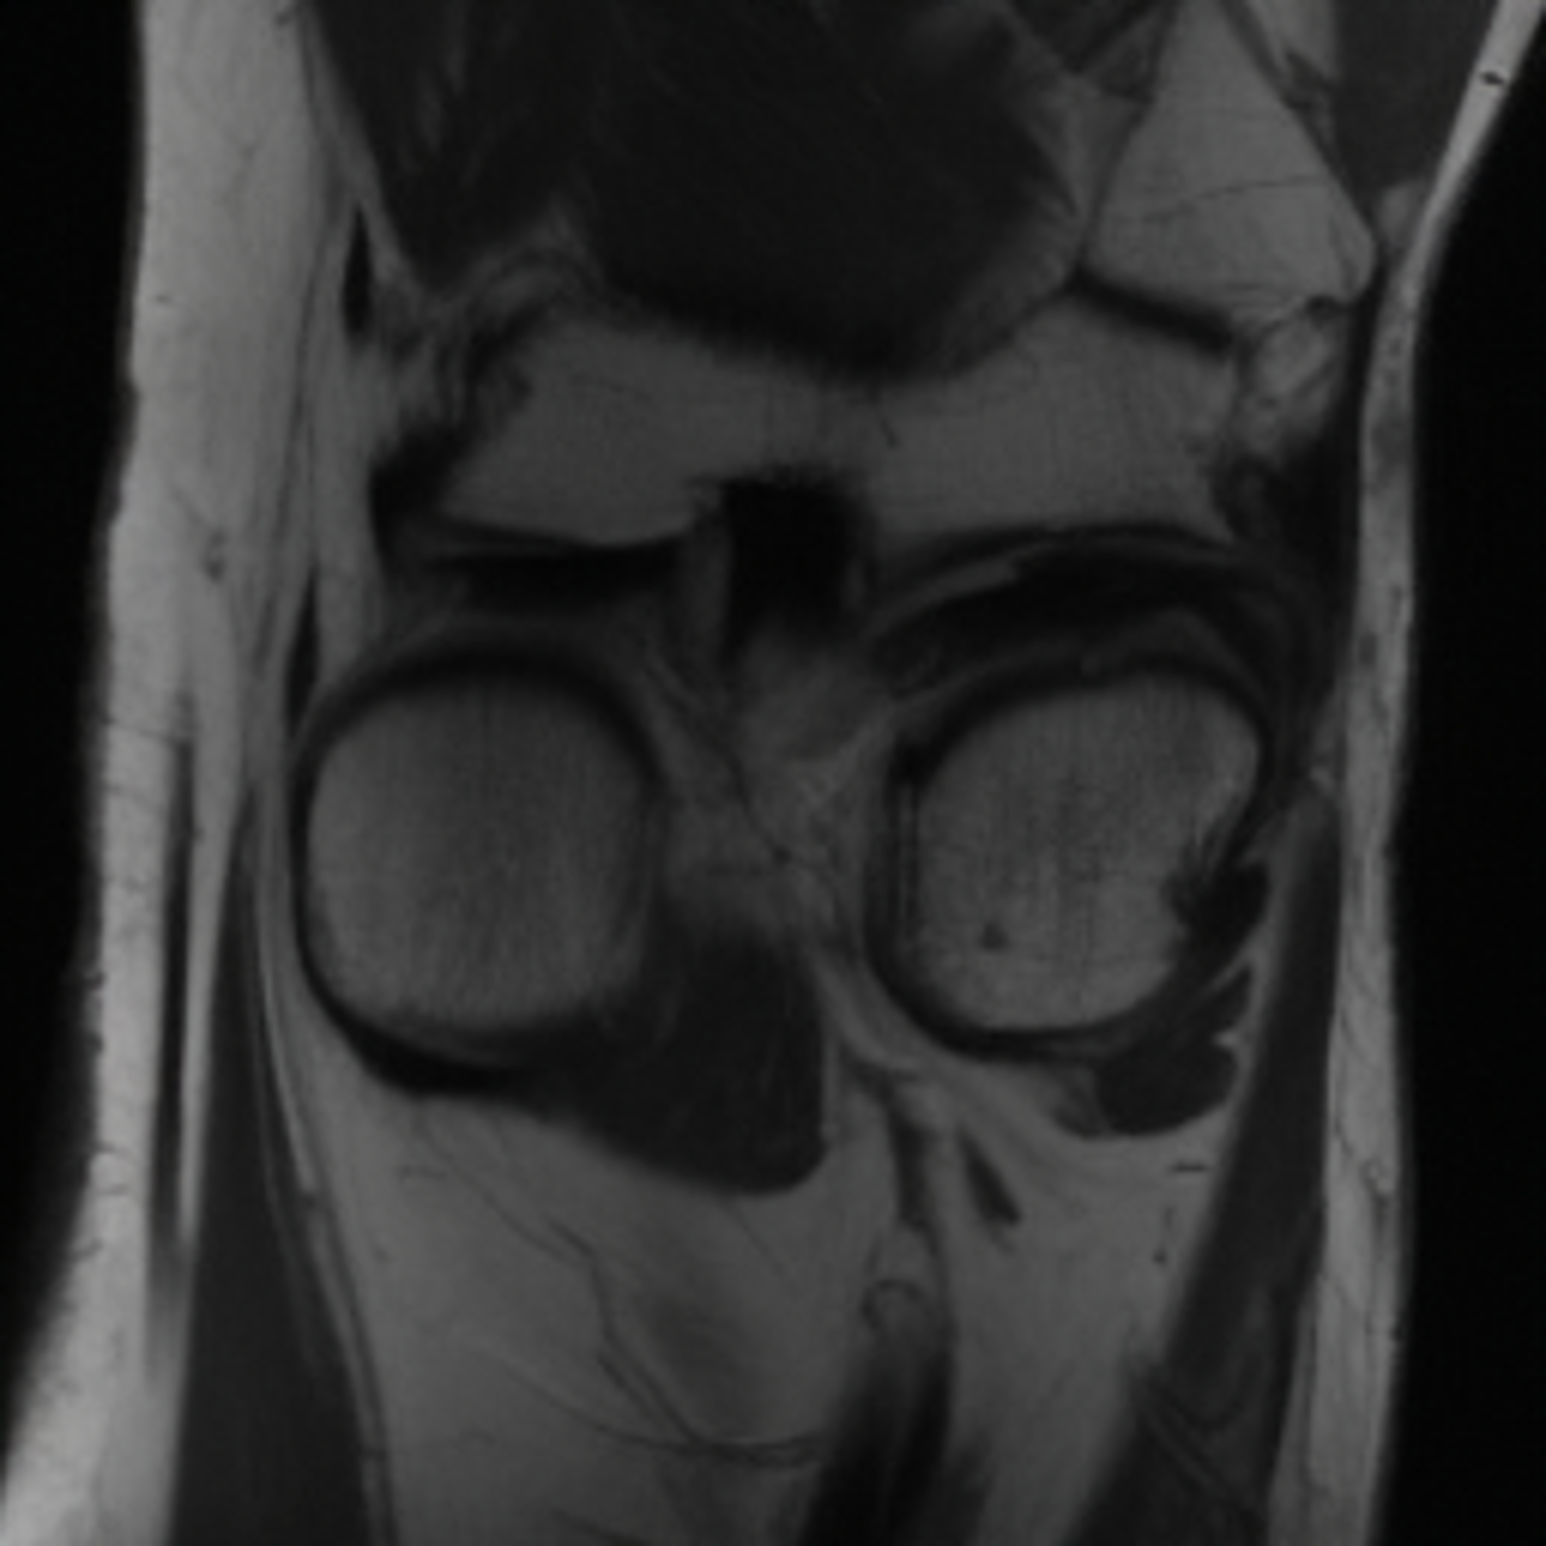

One way to test the generalization capability of the trained X-Diffusion is to test it on a completely different domain from an MRI dataset not seen during training. We report the single-slice results on the test set of knees from NYU fastMRI [33, 80], using the X-Diffusion trained on the BRATS brain MRIs. The test PSNR result is 34.17 and an example is shown in Figure 8. It shows how successfully X-Diffusion can generate knee MRIs (out-of-domain) despite being trained on brains.

Small Knee MRIs clinical study. To qualitatively assess how realistic our generated knee out-of-domain 3D volumes were (produced from a single slice), we gave 20 generated examples alongside their real MRI counterparts to an expert orthopedic surgeon J. F.. He was then asked to identify the real example from a set of 20 MRI pairs. The surgeon correctly identified the real MRI in only 10 out of 20 pairs, could not decide in 3 pairs, and misidentified the generated MRI as real in the remaining 7 pairs. This further validates the generated out-of-domain MRIs.

Objective. To see if recent generative AI technologies for MRIs (X-Diffusion) are relevant to knee diagnosis. The goal is to validate our pipeline for reconstructing full MRIs from one/few slices with high precision and evaluate its usefulness for clinical assessment of knees. Given expert grading of how abnormal a knee is, we will compare the score given for degeneration of knees between the two sets of knees with and without AI generated knees.

Specific Aim. Grade how abnormal a knee is on an external set of 50 reconstructed MRIs from single slices or two slices each using X-Diffusion. Then, compare the score for knee degeneration between the annotated original set of 50 samples from humans and see how they are correlated. First, experts will grade degenerative knees on MRI. Then we test X-Diffusion on the same sampled graded. Given any single slice(s) from a degenerate knee we generate synthetic knees. Finally, we compare the score given as grading for degeneration of knees between the two sets of knees with and without AI generated knees.